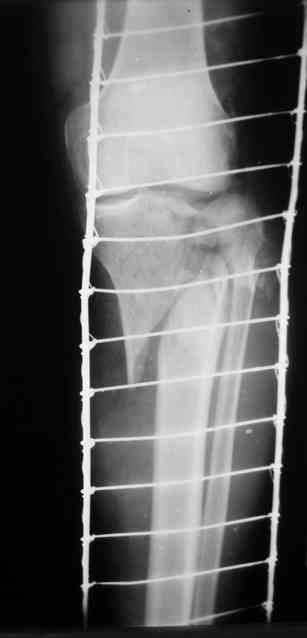

Р-граммы и фото за 4.05.2007 - 7-е сутки после операции.

Ход операции - линейным разрезом по передней поверхности голени обнажена зона ложного сустава большеберцовой кости. От кости отсепарованы медиально м/ткани. Из зоны ложного сустава убраны рубцовые ткани, мобилизован дистальный отломок. По передней поверхности удалены два осколка, связанных грануляциями. Произведено удаление грануляционной ткани из проксимального отломка (на вид сине-серого цвета), "чистого" гноя не было. Затем произведено наложение аппарата и репозиция отломков. По передне-медиальной поверхности образовался дефект до 4х2х2 см + полость в проксимальном отломке. Удаленные осколки очищены от грануляций, уложены в место дефекта, зажаты между отломками. После иссечения раны по передней поверхности, находящейся рядом с операционной раной, последняя ушита с большим натяжением.

Перелом мыщелка сросся. Проксимальный отломок очень порозный.

На перевязках - из раны небольшое кол-во сукровичного отделяемого. Отек голени умеренный, состояние кожи на фото.

Аппарат видел, репозиции не заметил. О "наложенном" аппарате: спицы в проксимальном отломке б\берцовой кости проведены очень низко, и опять только две, как и в первом аппарате. Почему только одна спица в дистальном парафрактурном кольце? Проксимальная база на бедре должна улучшить стабильность проксимального фрагмента tibia? Ничего подобного двумя спицами в одной базе при таком длинном рычаге вы не добьетесь, а вот совсем потерять движения в коленном суставе они почти гарантируют.

О репозиции: мыщелок сросся и слава Богу, но основные отломки фиксированы в вальгусном положении, собственно как и было, это критично. В чем состояла репозиция?

Выглядит тревожно и не дает повода для оптимистичных прогнозов.